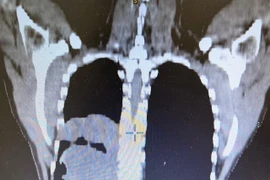

(khoahocdoisong.vn) - Trung thất được phân chia làm 3 phần: Trung thất trước, trung thất giữa và trung thất sau. Các cơ quan của trung thất có các biểu hiện bệnh tật riêng.

U trung thất trước chiếm tỷ lệ cao nhất, bao gồm u tuyến hung, u tế bào mầm… 30 – 50% các trường hợp u trung thất không có biểu hiện hoặc có một số biểu hiện không đặc trưng như: Đau ngực, khó thở, ho, sốt… Khối u vùng trung thất thường gây ra hội chứng chèn ép tĩnh mạch chủ, tim, phổi, nên rất nguy hiểm cho bệnh nhân bất cứ lúc nào. Với kỹ thuật mổ nội soi tại Bệnh viện Phổi T.Ư đã mang lại thành công và may mắn cho nhiều bệnh nhân.